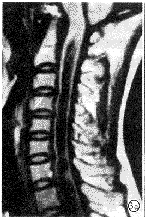

图1 脊髓肿瘤伴空洞症。a)平扫示C6-T2脊髓不均匀低信号,T2以下脊髓空洞;b)增强后示T2结节状强化。